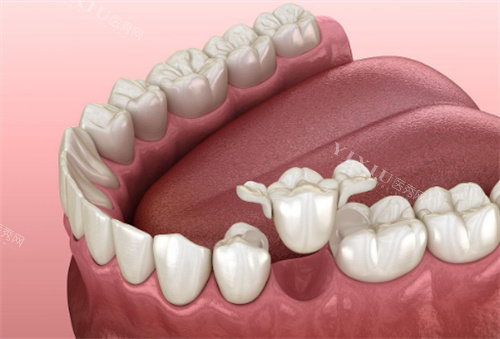

科室与特色项目

门诊按常见需求划分了种植牙、牙齿矫正、牙齿修复三大核心科室,覆盖从缺牙修复到牙齿美观的各类需求。其中,小切口种植牙是热门项目之一,采用精细操作技术,创口比传统种植小30%,术后肿痛轻,适合牙槽骨条件一般或怕疼的缺牙患者。之前有位65岁的张阿姨,种了两颗后说“当天就能吃软面条,疗养时间比想象中短”。